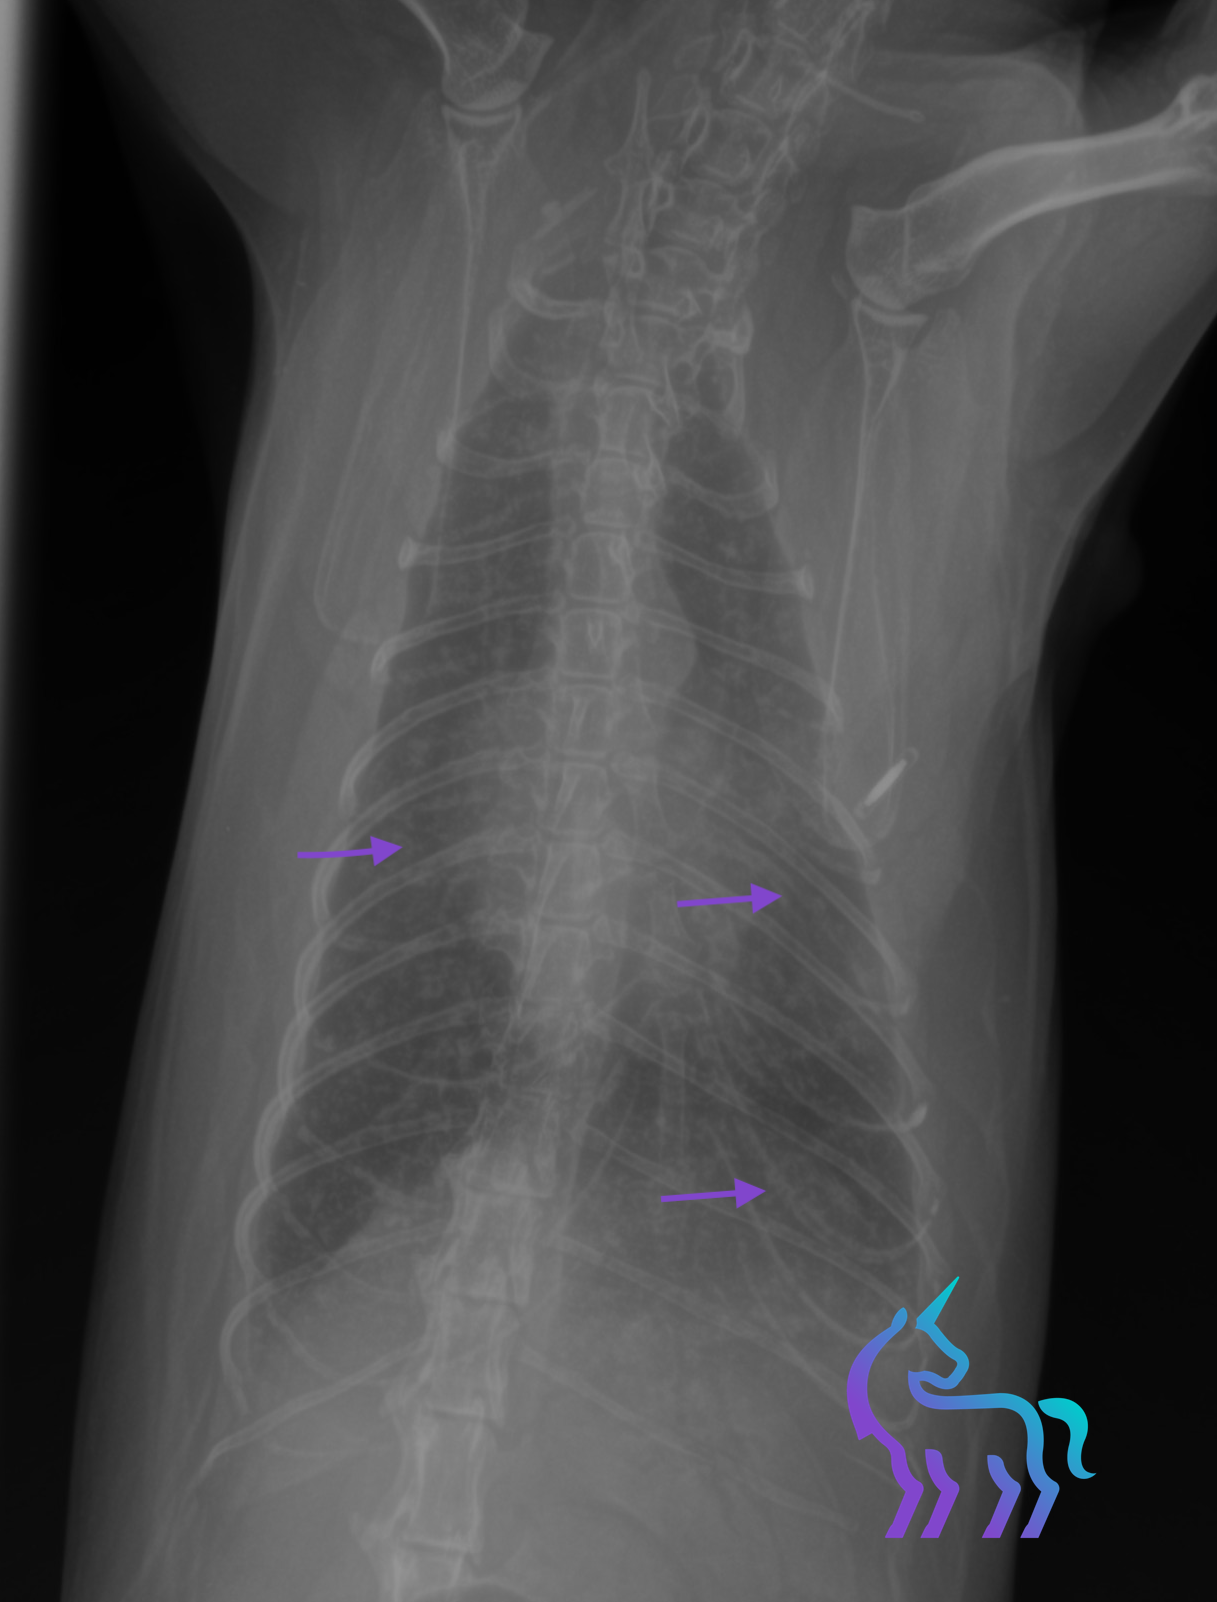

Dilatation diffuse de l’œsophage (Mégaœsophage)

Espèce : ChienRadiographies thoraciques montrant une dilatation diffuse de l’œsophage, confirmée par l’examen avec produit de contraste.

Aspect compatible avec un mégaœsophage, sans anomalie cardiovasculaire associée sur ces clichés.

Diagnostic retenu : La radiographie permet ici d’objectiver le diagnostic de mégaœsophage et d’orienter la prise en charge clinique.